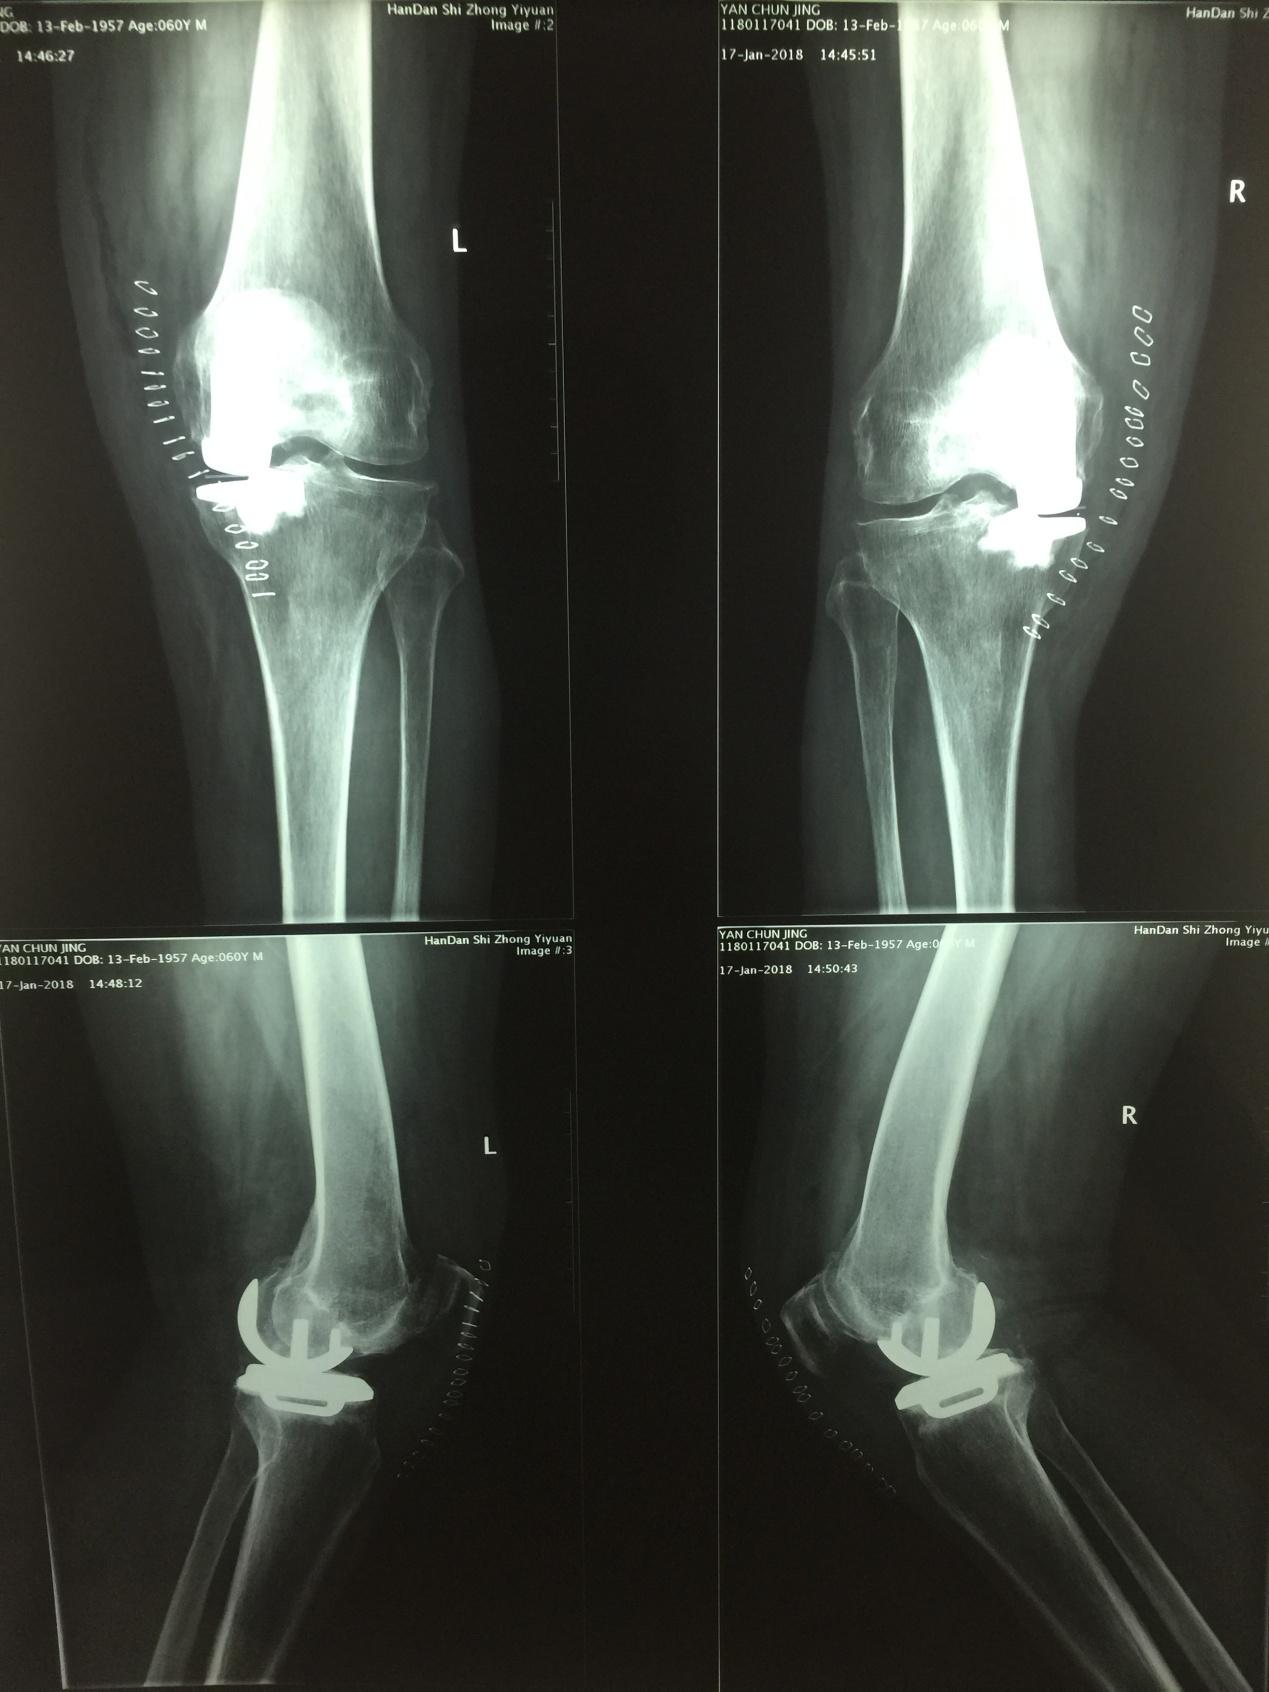

随着人口老龄化,膝关节骨关节炎的发病率逐年增高,膝关节骨关节炎的治疗方法很多,探索膝关节骨关节炎的阶梯化治疗成为必然。1月16日下午,我院骨六科主任甄红军,带领蒿俊行主治医师、刘章主治医师,成功完成医院首例一期双膝关节骨关节炎单髁关节置换术。标志我院在膝关节骨关节炎保膝治疗领域又上一个新台阶。 患者闫先生,男,60岁,双膝关节疼痛10余年,关节内翻畸形、活动受限,经口服药物、关节腔注射玻璃酸钠、关节镜清理术后、症状反复发作,影响生活和工作,不能正常行走。来到中医院就诊后,骨六科甄红军主任经科室会诊讨论后认为:患者男性60岁,主要表现为双膝关节内侧疼痛,X线片显示膝关节内侧间室退变严重、外侧关节间室、膝关节交叉韧带和髌股关节良好,决定给患者行双膝关节单髁关节置换手术,手术顺利,术后患者恢复良好。 膝关节单髁置换术:是应用MIS微创技术,不破坏膝关节韧带结构,手术创伤小、术后关节活动度更大、恢复快,病人住院时间短,属于保膝治疗手术。 其适应症:1、膝关节单间室间隙变窄(负重位相),不合并外侧间室和髌骨关节的退变 2、前交叉韧带功能完好 3、年龄在55岁以上,从事轻体力活动的人群 4、膝关节关节内的畸形、屈曲强直畸形角度﹤15。